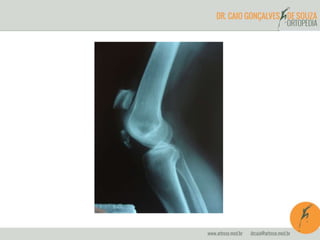

Radiografia

Tratamento

Conservador

Cirúrgico